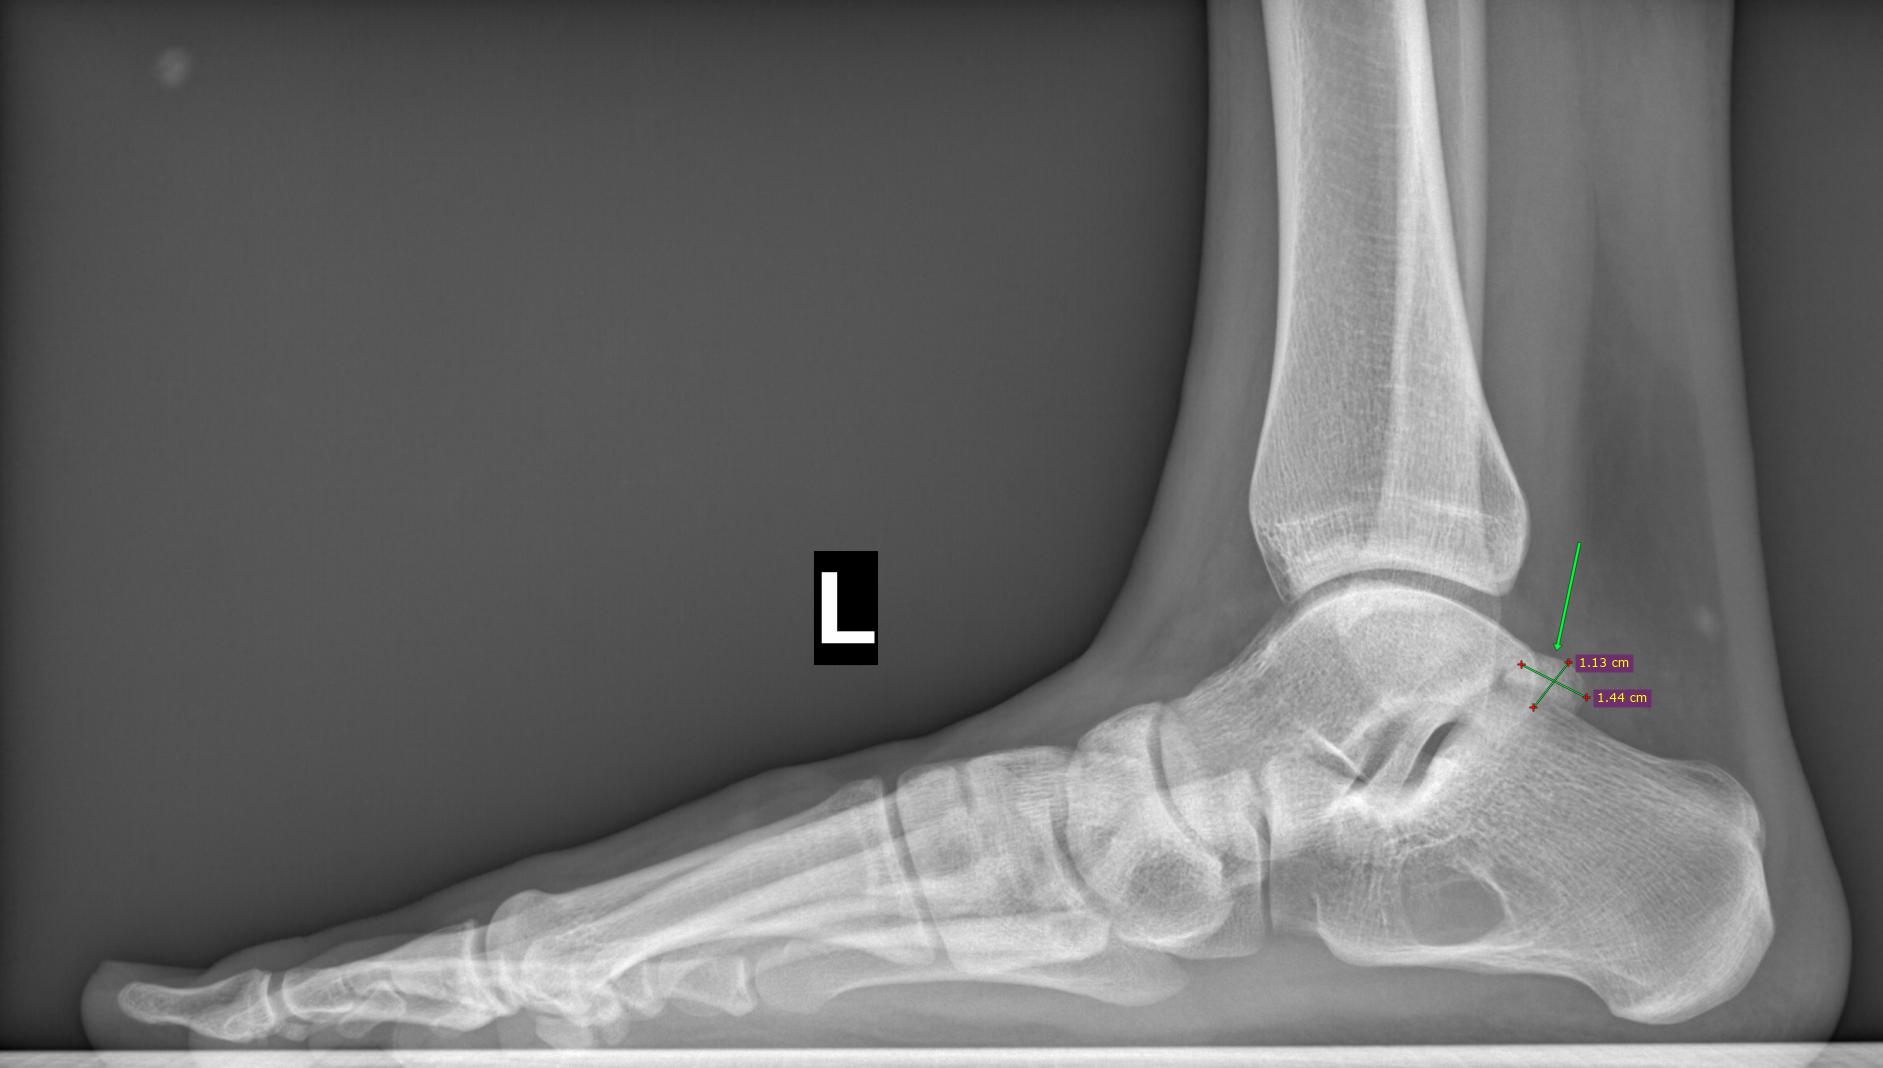

По заднему контуру таранной кости визуализируется добавочная кость- os trigonum размером 1.1х1.5см,наиболее вероятно вызывающая импиджмент-синдром заднего отдела голеностопного сустава.